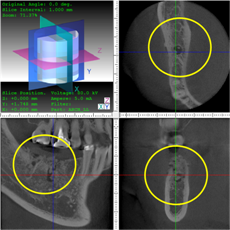

抜歯のう胞摘出

Perio Wave+Er:YAGレーザー+コールドレーザーで治療した箇所の経過です。

左から直後、1ヶ月経過時、2ヶ月経過時の画像です。

骨再生の確認をした際の動画です。

画像をクリックすると、youtubeにジャンプします。

骨再生

骨再生した箇所にインプラントを埋入します。

CTで治療計画を綿密に練ったうえで行いました。